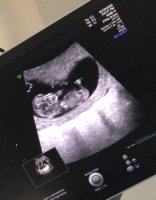

Her er nurket som jeg fikk kikket litt på i går! ❤ regnet ut til å være 9+2 i går! :) en dag fra eller til spiller ingen rolle ❤